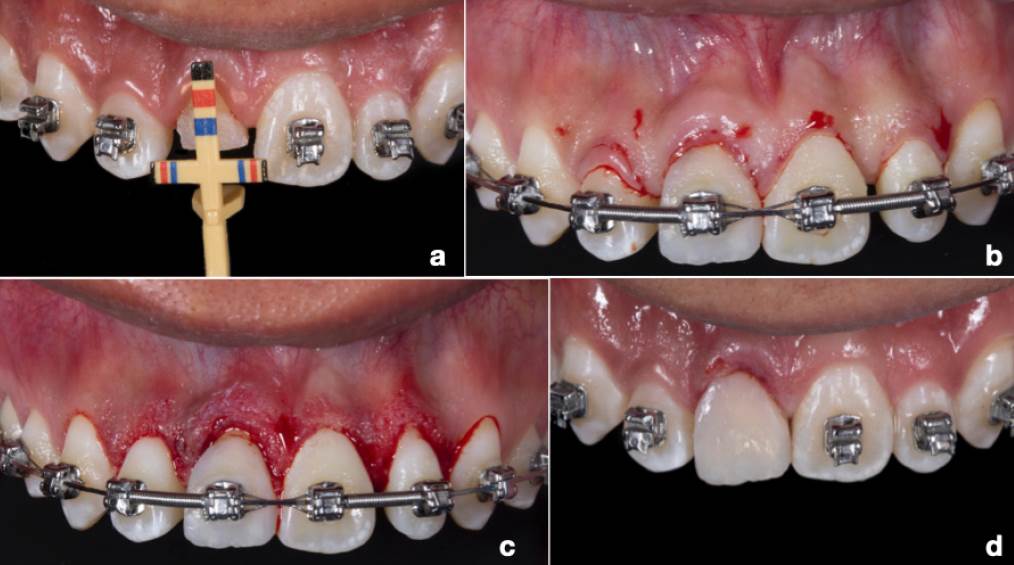

Después de una semana se obturó con gutapercha y se colocó una obturación temporal de más de 6mm durante una semana. Después del tratamiento de conductos, se realizó una reconstrucción temporal del diente, con la finalidad de continuar con la extrusión. Una vez lograda, se elaboró una mejor reconstrucción dental con el objetivo de mejorar la estética y sujeción. El resultado final de la extrusión fue de 2mm y se obtuvo después de 8 meses. Una vez que el diente se encontraba en la posición correcta dentro del arco dental (Figura 1.C) y antes de iniciar la rehabilitación post-endodóntica, se llevó a cabo una gingivectomía para eliminar el excedente de tejido blando post-extrusión e ir conformando el margen gingival de los dientes 11 y 12 (Figura 2.A-B).

Figura 2 Procedimiento periodontal y provisionalización. A. Mediciones pre-quirúrgicas. B. Remodelado gingival. C. Resina estratificada como provisional durante el tratamiento de ortodoncia. D. Colocación de provisional definitivo.